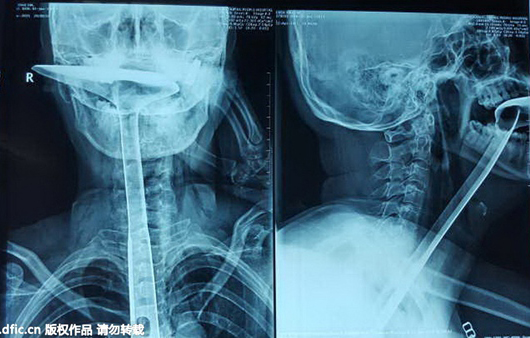

Hình ảnh chụp X-quang.

Chen được đưa tới bệnh viện Kuanghua và phải trải qua hai ca phẫu thuật. Các bác sĩ lấy chiếc xẻng nấu ăn ra khỏi cổ họng thành công nhưng phải cắt đi đoạn thực quản dài 20cm đã bị tổn thương nghiêm trọng. Rất may tính mạng người phụ nữ này không bị đe dọa. Chen đang hồi phục và sẽ xuất viện sau hai tuần nữa.